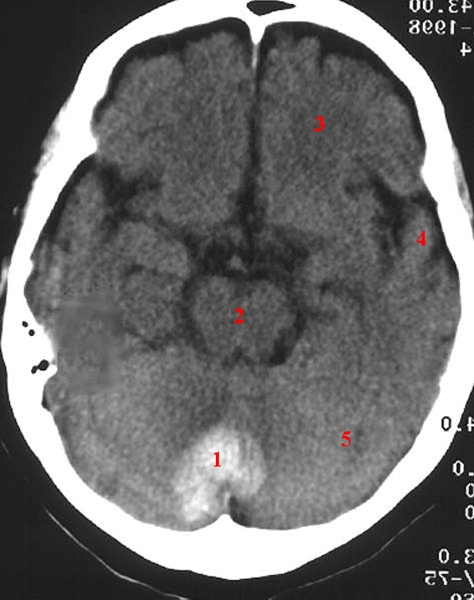

CT af hjernen (axialbillede) uden kontrast. Blødning mellem de to cerebellare hemisfærer.

1. Blødning

2. Hjernestamme

3. Frontallappen

4. Temporallappen

5. Cerebellum